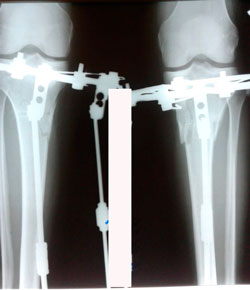

на фиксации

Дата операции - 21.01.2020

Дата снятия аппаратов - 12.05.2020

Срок сращения - 111 дней.

рентген пере снятием аппаратов.